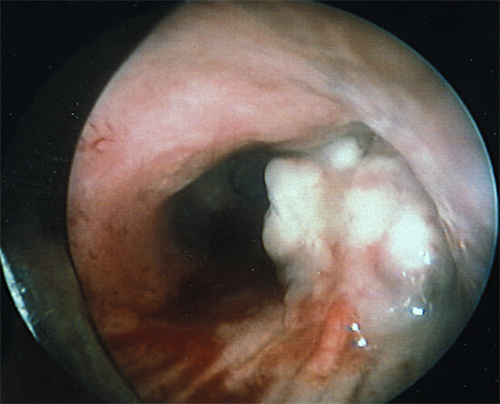

Figure A: Bronchoscopic View of a Central Airway Tumor Involving the Right Upper Lobe of the Lung.

Use of other staging modalities should be done selectively according to the structures of interest for a given tumor. Bronchoscopy is an invaluable tool in the evaluation of centrally located tumors. It aids in determining the extent of surgical resection by direct evaluation of the degree of airway involvement, which is critical for determination of resectability and consideration of bronchoplastic techniques (Figure A). The procedure should be performed at the time of planned surgical resection by the operating surgeon so that the endoscopic examination contributes the greatest value in surgical planning. Bronchoscopy combined with ultrasonography (endobronchial ultrasound [EBUS]) can yield additional important staging information. Fine-needle aspiration may be performed with the aid of EBUS or endoscopic ultrasound via esophagoscopy, and offers the opportunity for direct sampling of suspicious mediastinal lymph nodes and evaluation of the esophagus for local invasion. Sensitivity and specificity of endoscopic ultrasound for detecting metastatic mediastinal disease on pooled analyses are 78% and 71%, respectively, with an overall accuracy of 80% if one includes lesions visible on CT but not on ultrasound.[28] Echocardiography can be used in the preoperative clinical staging period to assess for cardiac or great vessel involvement, and it can also be used for real-time assessment via intraoperative transesophageal echocardiography (TEE). In small series, TEE has an accuracy of 100% for predicting cardiac involvement in patients undergoing surgical exploration.[29]